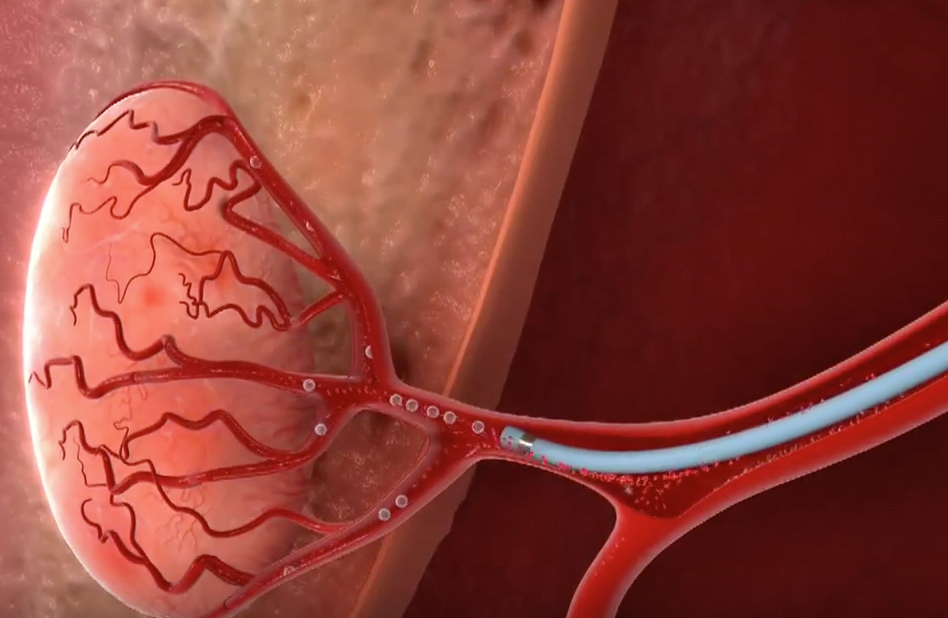

Хирургические процессы при эмболизации гемангиомы на фото